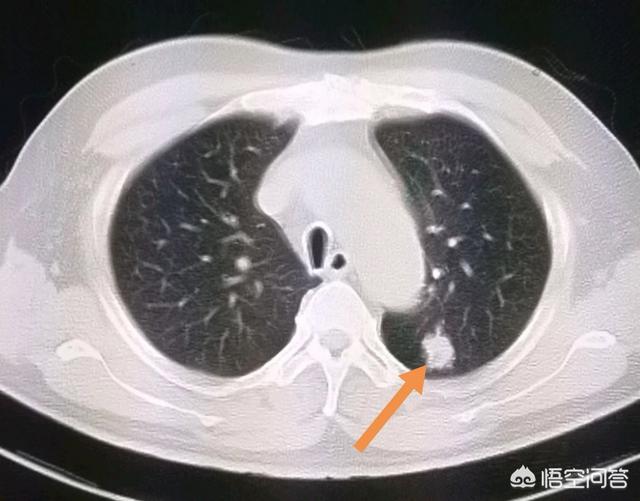

上图就是一位比较早期的食管癌病人。手术成功切除食管中下段。把食管上段和胃吻合。已经八年半了。恢复得很好。

这是一位73岁的大细胞癌。肿瘤9厘米。手术做了好几个小时。成功切除!